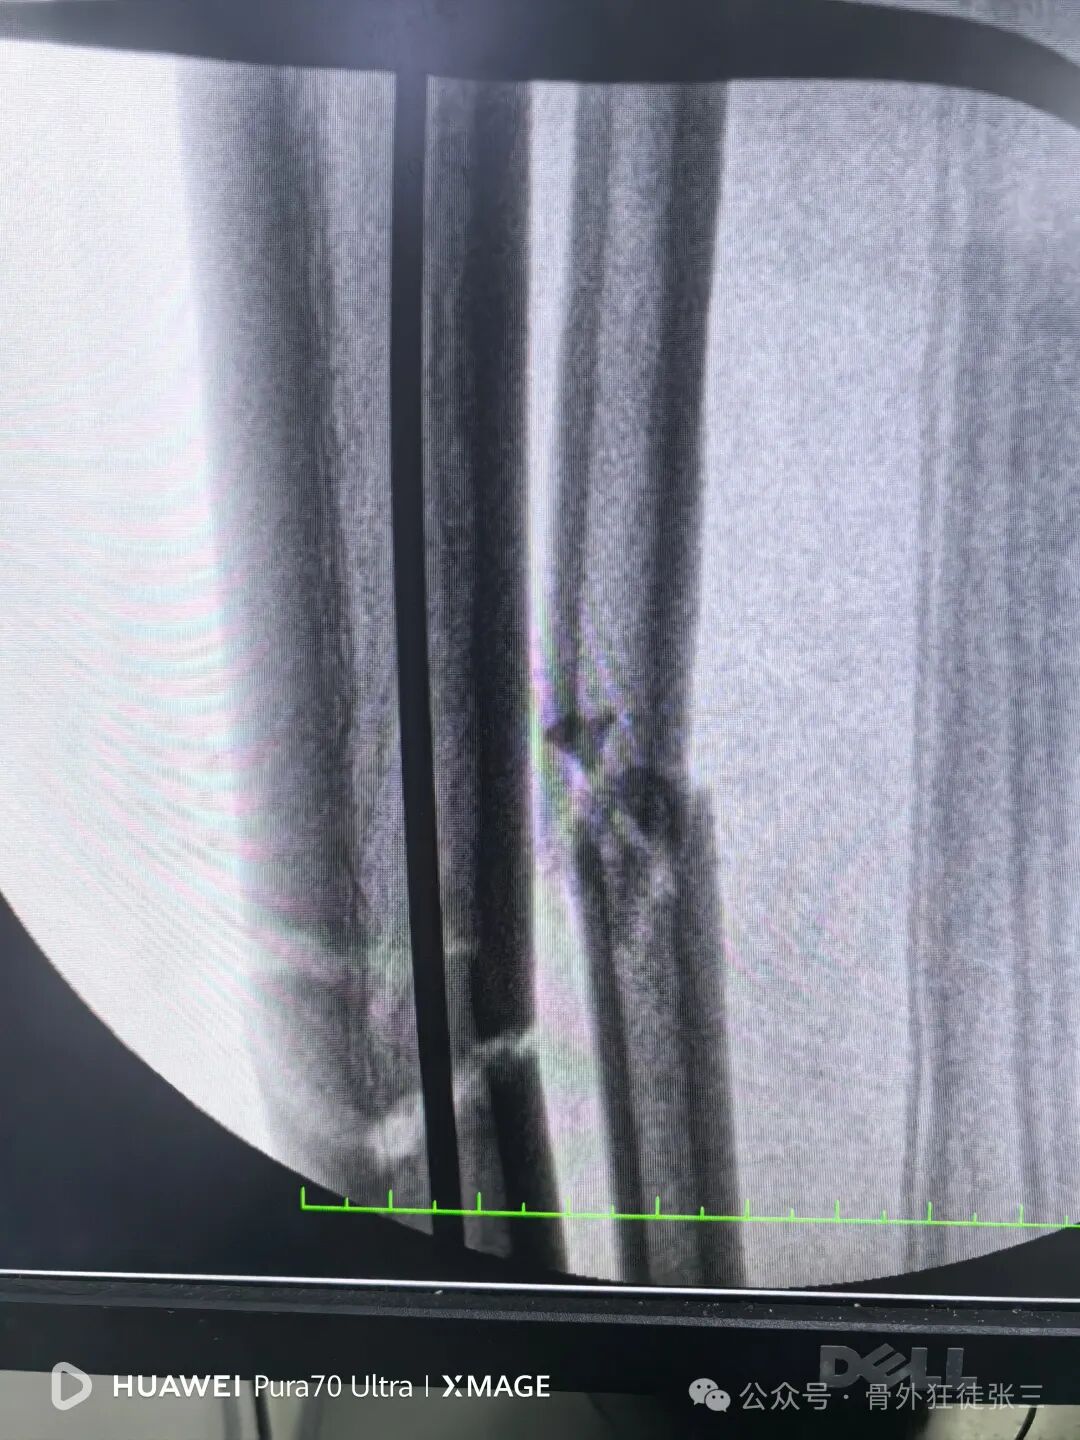

远端安装瞄准架

骨折间隙顺利缩小

侧位复位良好